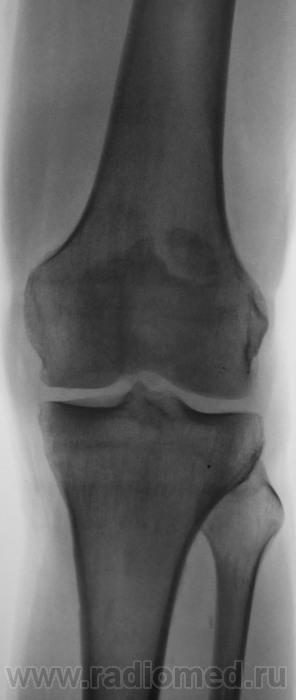

Травма. Направлен на рентгенографию коленного сустава

Несросшийся апофиз надколенника, деструкции не вижу

Без костных травматических изменений.

Такое развитие надколенника. Хотя может быть и травматический разрыв фиброзных сращений.

Подумала и решила исправить запись -исход остеохондропатии надколенника

А, может быть просто пателла бипарцита?

Можно уточнение ? Край основной массы надколенника неровный, углы заострены и щель выглядит неравномерной -это обычная картина при удвоении надколенника ?

И мне это не понравилось. И по боковой - впечатление о смещении фрагмента.

Мужчина 39 лет, жалоб нет. Обратил внимание на разницу с другим коленным суставом (выпирает). Второй сустав на снимке без изменений. Травм утверждает, что не было.